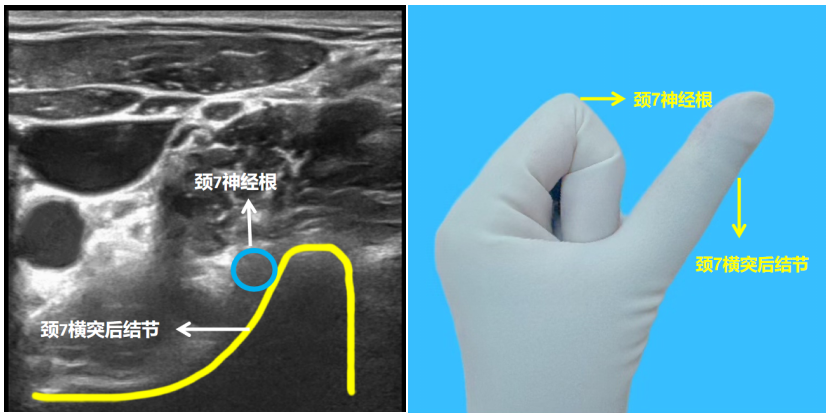

如何在超声引导下快速精准定位星状神经节?星状神经节位于C6和C7椎体之间、颈长肌表面。C7横突与SG的距离最近,是标定SG体表投影的最佳骨性标志,但是C7横突没有前结节,椎动脉未受椎动脉孔保护,在此穿刺容易伤及椎动脉。临床多以C6横突为解剖定位,从而决定星状神经节阻滞穿刺点。下面通过一套简单易懂的手势,学会快速精准定位星状神经节[5]:首先将探头放至锁骨上窝,比出“大拇指朝上”的手势,大拇指为C7横突后结节,屈曲的四指为C7神经根,探头向上继续移动,比出形似“八”的手势,大拇指为C6横突后结节,食指为C6横突前结节,屈曲的三指为C6神经根,确定C6横突后,缓慢移动探头,直至可以清楚地显示颈长肌、椎前筋膜,星状神经节阻滞点位于颈长肌前方、椎前筋膜深面。

图5:颈7横突短轴图和手势图

图6:颈6横突短轴图和手势图